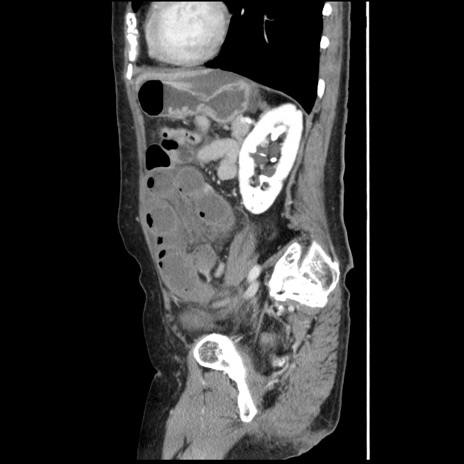

冠状断像

【症例】80歳代女性

【主訴】腹痛

【現病歴】8時間前から腹痛あり来院。

【既往歴】糖尿病、脂質異常症、子宮体癌にて子宮全摘術

【身体所見】意識清明・会話良好だが腹痛で苦悶様、全腹部にわたって反跳痛と圧痛あり

【データ】WBC 13600、CRP 0.14、LDH 224、CK 90